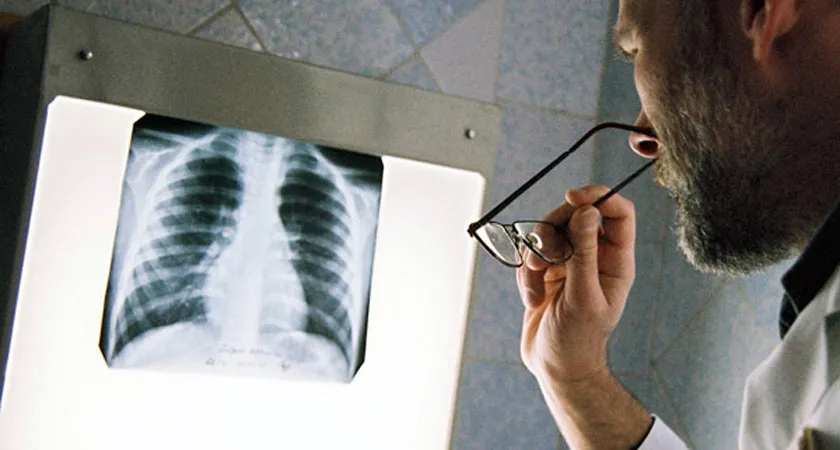

Правительство РФ утвердило план реализации государственной программы «Развитие здравоохранения».

Как сообщает пресс-служба кабинета министров, Распоряжение от 4 сентября 2014 года №1727-р содержит перечень наиболее значимых для реализации программы контрольных событий, сроки их достижения, а также данные об ответственных федеральных органах исполнительной власти.